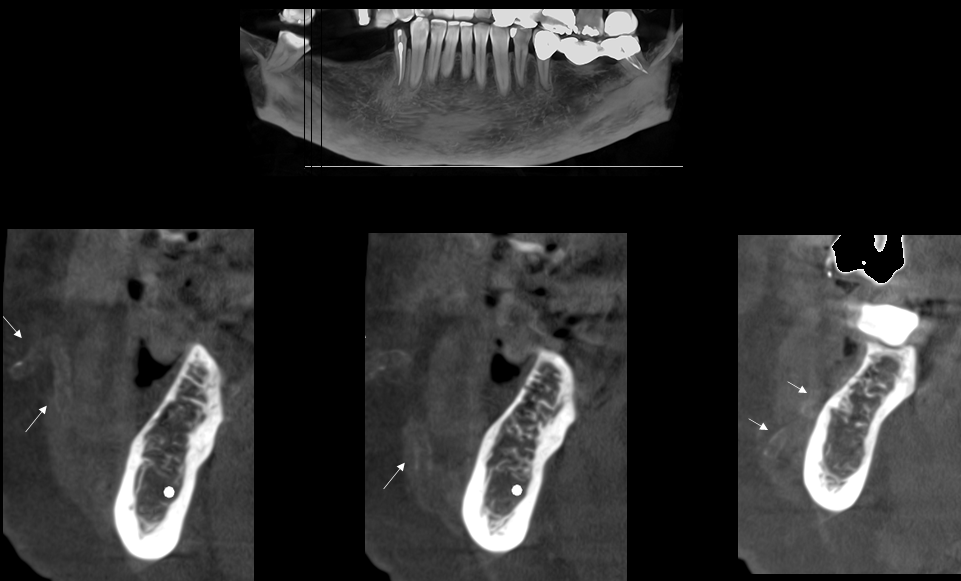

A la evaluación de la tomografía volumétrica (cone beam) bimaxilar en los cortes axiales (Figura 2) y transaxiales (Figura 3) se observa una imagen hiperdensa tubular de trayecto serpentiginoso con recorrido desde escotadura antegoneal al espacio bucal de lado derecho compatible con mineralización de tejidos blandos.

CORTES TRANSAXIALES